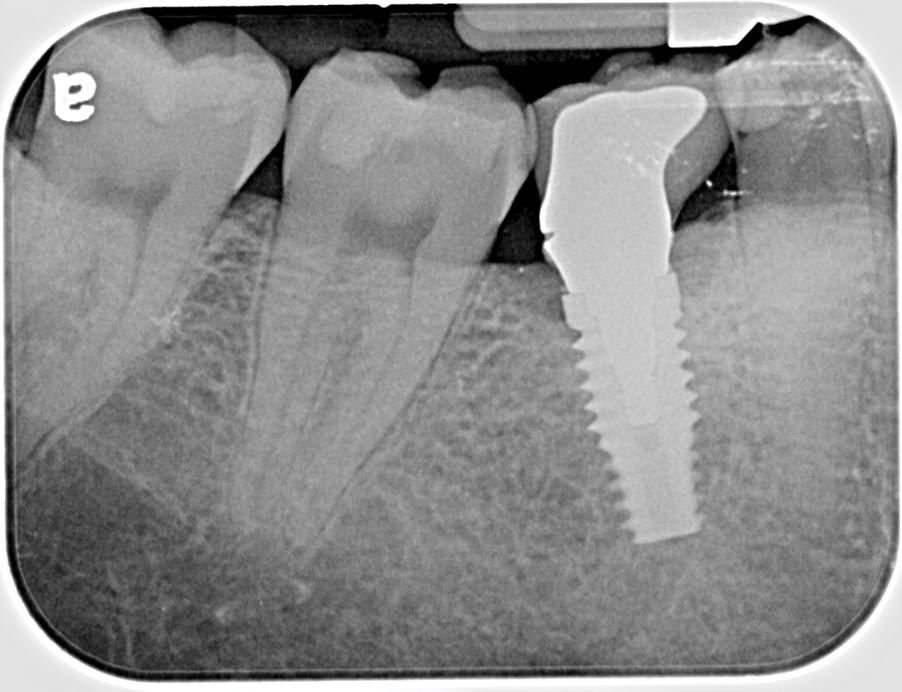

Fig 13. Radiograph depicting peri-implantitis.

Figure 13

Excess Cement Leading to Peri-implantitis

If all implant-supported crowns could be designed for screw retention, no discussion of excess cement would be necessary. However, screw retention is not always possible depending on the location of the access opening and because of the unesthetic appearance in anterior restorations or the mesial/distal angulation of the implant compromising the path of insertion (Figure 12). Residual cement left after crown cementation on implants can lead to peri-implant inflammation, peri-implantitis, and eventual loss of the implant (Figure 13 through Figure 15).25 The presence of lingering excess cement can encourage the development of bacterial colonization and peri-implantitis. Conversely, when too little cement is used, voids in the cement layer can occur and the prosthesis can become loose.26 The deeper the implant crown margin, the more difficult it is to remove excess cement.27

Radiopaque cements that contain zinc phosphate and zinc oxide (with and without eugenol) should be considered to help identify excess interproximal cement; however, this should be used secondarily to proper margin height and careful removal of cement during cementation. Resin cements lack the same opacity as zinc-containing cements and have been shown to be the most difficult to remove.28 Often in the process of removing this excess cement, the abutment surface becomes scratched and damaged, potentiating further plaque accumulation.29